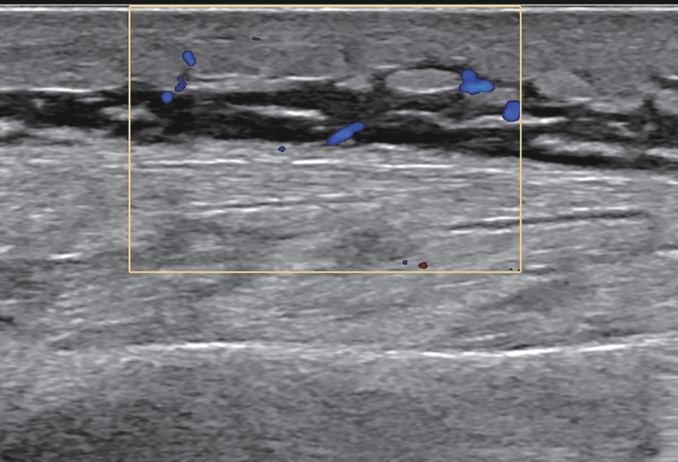

Correlation between liver fibrosis degree and carotid plaque in patients with lean metabolic dysfunction-associated fatty liver disease

Shuai ZHANG, Shoulu JIN, Wanqing LI, Xijing SHI, Hao LIANG, Hao DONG, Dailong LU, Ying ZHU, Xiaoxing XIANG, Jun LIU

2026, 42(2): 319-325. DOI: 10.12449/JCH260212

Abstract(204) HTML (68) PDF (3293KB)(80)

Abstract:

Objective  To investigate the association between noninvasive liver fibrosis markers and carotid plaque (CP) in patients with lean metabolic dysfunction-associated fatty liver disease (MAFLD), and to provide a basis for screening high-risk populations.  Methods  A total of 957 patients with lean MAFLD who underwent physical examination in Subei People’s Hospital from January 2021 to June 2023 was enrolled as the observation cohort, with the presence or absence of CP as the outcome, and fibrosis-4 (FIB-4) index and nonalcoholic fatty liver disease fibrosis score (NFS) were used to assess liver fibrosis degree. The independent-samples t test was used for comparison of normally distributed continuous data between two groups, and the Mann-Whitney U test was used for comparison of non-normally distributed continuous data between two groups; the chi-square test was used for comparison of categorical data between two groups. The multivariate logistic regression analysis, the restricted cubic spline analysis, the receiver operating characteristic curve, and the mediation effect analysis were used to investigate the association between liver fibrosis degree and CP.  Results  The prevalence rate of CP was 36.6% in the lean MAFLD population. Compared with the non-CP group(n=607), the CP group (n=350) had a significantly higher proportion of male patients, a significantly higher proportion of patients with smoking/diabetes/hypertension, and significantly higher levels of age, creatinine, blood urea nitrogen, triglycerides, fasting blood glucose, aspartate aminotransferase, aspartate aminotransferase/alanine aminotransferase ratio, NFS, and FIB-4 index, as well as significantly lower levels of platelet count and albumin (all P<0.05). The multivariate logistic regression analysis showed that after adjustment for confounding factors, FIB-4 index (odds ratio[OR]=2.979, 95% confidence interval[CI]:2.141 — 4.219, P<0.001) and NFS (OR=1.747, 95%CI: 1.499 — 2.046, P<0.001) were positively correlated with CP. Both FIB-4 index and NFS had a good value in predicting CP. Hypertension had a significant indirect effect on the prevalence rate of CP through its impact on liver fibrosis markers, and its mediating effect accounted for 39.5% — 40.8% of the total effect (P<0.001).  Conclusion  In patients with lean MAFLD, NFS and FIB-4 index are significantly positively correlated with the prevalence rate of CP, and they can be used as potential epidemiological predictive indicators. Liver fibrosis markers may play a mediating role in the association between hypertension and CP. Interventions targeting hypertension and liver fibrosis markers may help to prevent and delay the progression of CP.